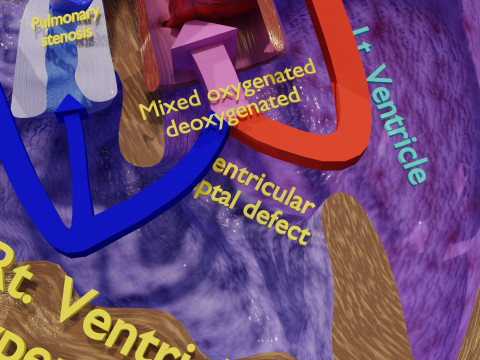

The model meshes include adult circulation versus circulation in Tetralogy of Fallot (TAF), arrow labels and text labels. The blood flow in a patient with Tetralogy of Fallot is outlined in this model. To contrast it to normal blood circulation a separate model of normal circulation is included. The Tetralogy of Fallot (OVER RIDING OF AORTA, PUL STENOSIS, VENTRICULAR SEPTAL DEFECT, RIGHT VENTRICULAR HYPERTROPHY), fossa, ligament teres , venosus, and arteriosus are duly depicted with proper labelling and blood flow directional arrows. Excellent model for teaching, demonstration and knowlegde of human body. The models include both procedural and image textures blend files separately. The texture file include diffuse, roughness and normal png and jpeg based on non overlapping UV maps.